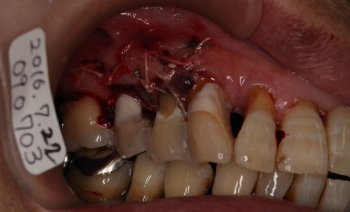

| 2016年07月22日 不良肉芽除去、根面清掃 骨補填剤の充填等 |